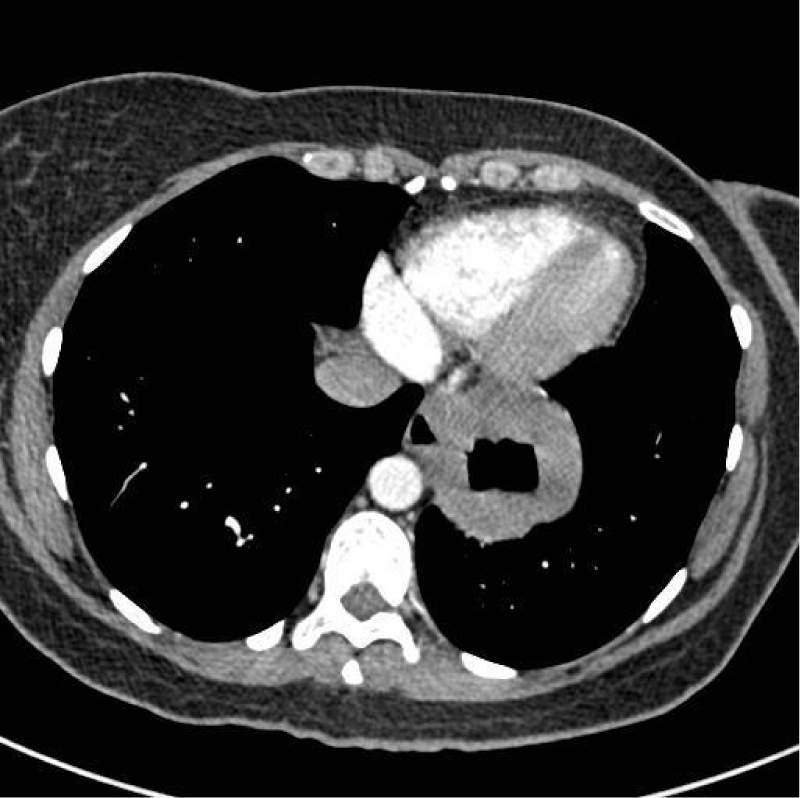

She initially had a Chest X-Ray, which showed a 5 cm, round and well-defined shadow behind the heart suspected to be of HH. This was followed by an enhanced Computed Tomography (CT) Thorax (Figure 1) that showed the CXR abnormality corresponded to a possible 6 cm sequestered lung segment. After discussion in the respiratory Multidisciplinary Team (MDT) meeting she was investigated further with a bronchoscopy. However, the bronchoscopy was normal and bronchial washings did not show any malignant cells. A positron emission tomography computed tomography (PET/CT) was then performed and showed a 6.5 cm thick-walled air filled mass in the lower lobe of the left lung with intense peripheral Fluoro Deoxy Glucose (FDG) uptake suspicious of a malignancy. A barium swallow showed the lesion seen on CT to be continuous with the lumen of the oesophagus (Figure 2). Following this, a large HH at 25 cm was visualised on an Oesophago Gastroduo Denoscopy (OGD) examination.